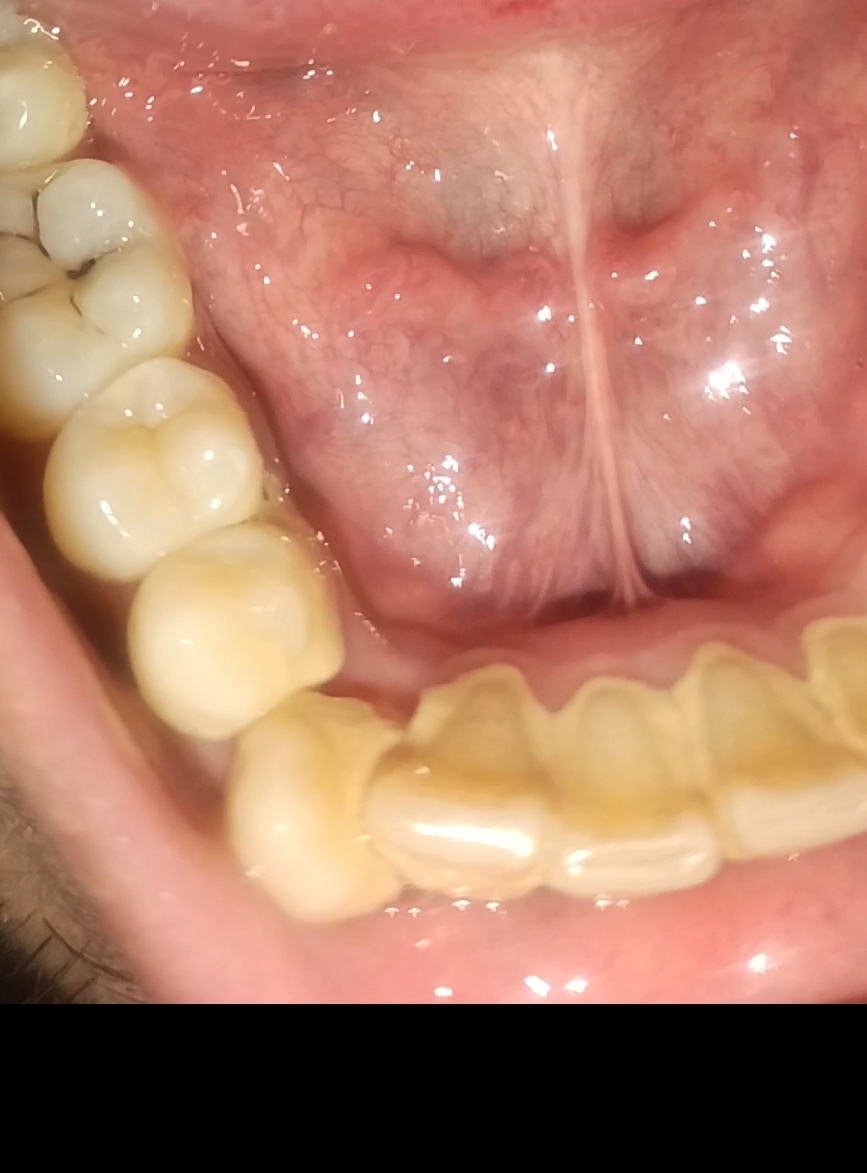

Asking for Self, Male, 26 years old, lahore

white-yellowish layer covering the teeth boundaries (except molar teeth, 1 front tooth has started to break down slowly through tiny oieces falling

these are tartar and plaque,u need scaling and polishing,

This is dirt that has accumulated and hardened over time. To clear these you need proper machine cleaning(scaling+polishing). The chipping off could be because of the oral hygiene protocols you started after noticing the problem.

Once proper cleaning is done you can maintain it by carrying out protocols necessary for daily oral hygiene.

It seems like you are dealing with tooth decay and plaque buildup, which has started to weaken one of your front teeth. This is a serious issue that requires immediate attention. The white-yellowish layer on your teeth is likely plaque or tartar, which can accelerate tooth decay if not treated.

We recommend you visit the clinic as soon as possible for a proper examination. This will allow us to assess the condition of your teeth and gums and suggest the most suitable treatment to stop further damage and restore your dental health

Visit nearby clinic and go for scaling and after this maintain hygiene and If you are using any additives try to stop it bcoz after treatment you may gain such condition after treatment there is no visible breakdown in pictures if so than dentist will go for filling.

Asalam u alikum...you need scaling and polishing.....its not tooth break down its calculus which has broken ....